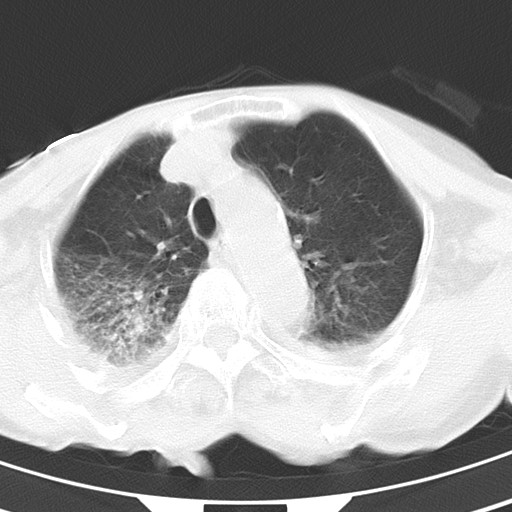

标题: CT21467:女,93岁,摔伤后检查。

女,93岁,摔伤后检查。

右肺炎症,心功能不全伴双侧胸腔积液,右下肺膨胀不全,食管裂孔疝,冠脉钙化,心包少量积液,左侧肋骨骨折,请上传骨窗.

右侧锁骨\\肩胛骨骨折、右侧湿肺,心功能不全伴双侧胸腔积液,右下肺膨胀不全,左膈破裂或食管裂孔疝,冠脉钙化,心包少量积液,请上传骨窗.

右肺炎症,心功能不全伴双侧胸腔积液,右下肺膨胀不全,食管裂孔疝,冠脉钙化,心包少量积液,左侧肋骨骨折,右肩甲骨粉碎性骨折。93岁,高寿哇!

右肺炎症,心功能不全伴双侧胸腔积液,右下肺膨胀不全,食管裂孔疝,冠脉钙化,心包少量积液,左侧肋骨骨折,右肩甲骨粉碎性骨折。